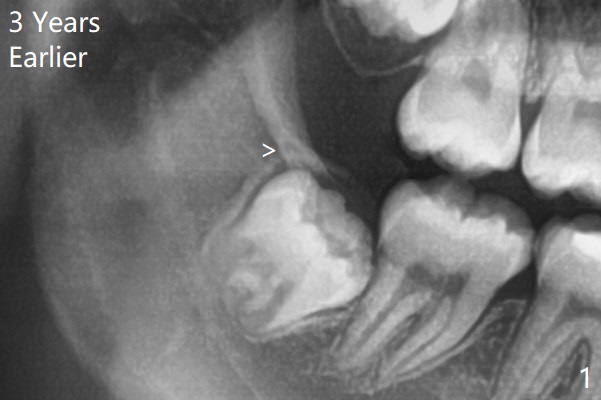

14岁外斜嵴尚未完全形成(图一:箭头);17岁时外斜嵴近中部分仍然被智齿阻挡而没有形成或者去除颊侧骨板时失去(图四),但是密度增加。这两个智齿不位于第二磨牙颊侧。